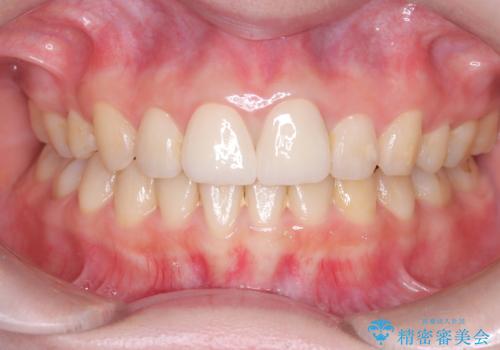

- 以前他院で治療した前歯の被せものの見た目の不満を主訴にご来院されました。レントゲンと診査の結果、被せものの不適合だけでなく、その土台となる歯の根管充填(根の治療の詰め物)が不十分であることが判明。再感染のリスクを避けるため、まず精密根管治療を行い、その後に最も審美性に優れたオールセラミッククラウンで修復する治療計画を立案しました。これにより、見た目の改善と歯の寿命の長期化を目指しました。

治療は、再感染の原因となっていた粗な根管充填材を丁寧に取り除く精密根管治療から開始しました。治療中はラバーダムと歯科用顕微鏡を使用し、根管内を徹底的に清掃・消毒。根の先まで緊密に薬を詰めることで、再発リスクを最小限に抑えました。根管治療の完了後、歯ぐきの状態を整え、周囲の歯と調和するオールセラミッククラウンを作製。金属を一切使わないため、透明感のある自然な仕上がりとなり、長年の見た目のコンプレックスも解消。歯の内部から表面までを根本的に改善することができました。